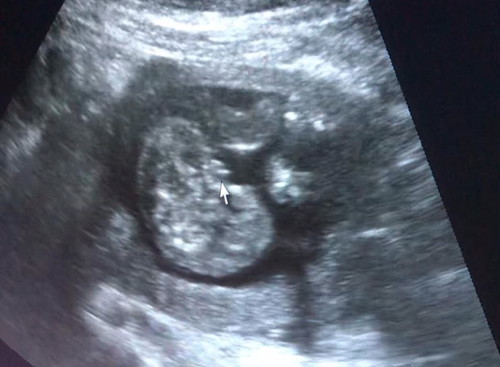

ซาวด์ตอน 19 weeks แบบนี้ เพศหญิงชัวร์ ใช่ไหมเอ่ย หมอบอก 95%